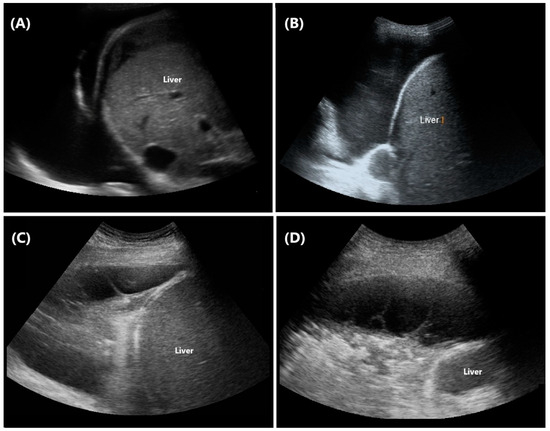

3.2. Pleural Effusion